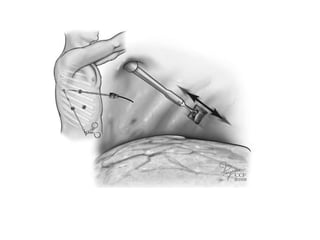

Tube Thoracostomy

• Tube thoracostomy is recommended for patients with large or

symptomatic SP and for most patients with SSPs

• Tech:

1. Through the fifth intercostal space in the midaxillary line

2. Apical placement speeds resolution, and a subcutaneous track prevents

“sucking air” during removal.

3. 28 French is preferable &directed toward apex

4. The chest tube is left in place between 24 and 48 hours

• Tube thoracostomy successfully resolves PSP in approximately 90% of

patients for the first occurrence, 50% for the first recurrence, and 15% after

a second recurrence.

• For this reason, tube thoracostomy is recommended only for definitive

management of PSP for the first event